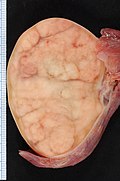

Gross

- Solid, white/tan.